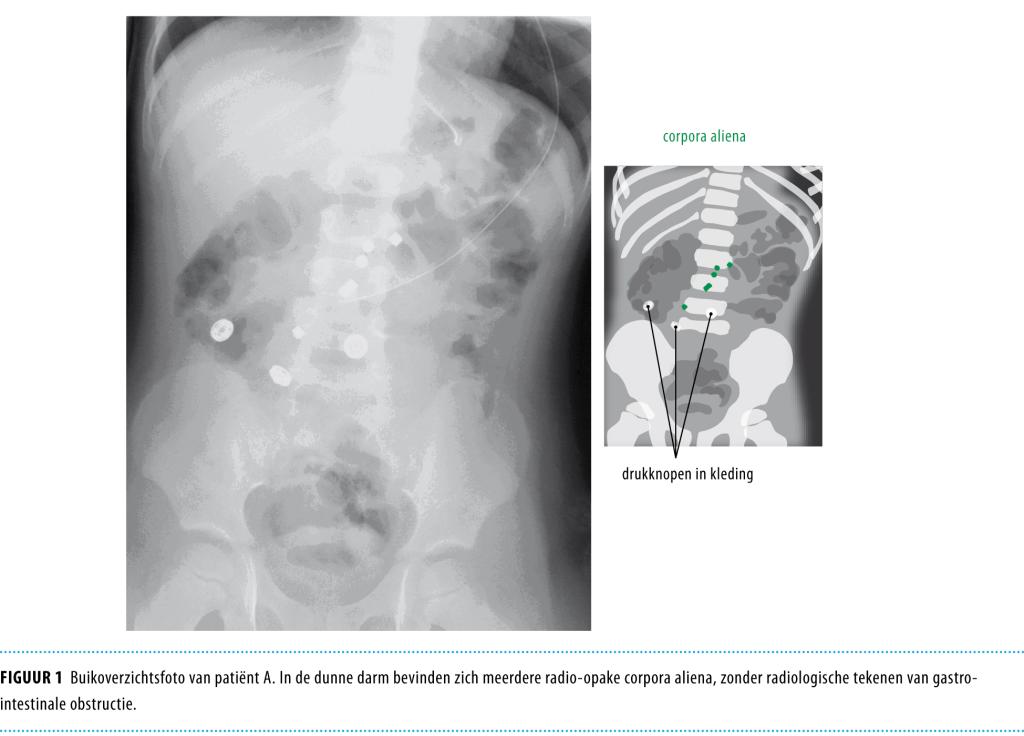

Een 3-jarige jongen werd naar de Spoedeisende Hulp gebracht vanwege buikpijn, misselijkheid en niet-gallig braken. Lichamelijk onderzoek toonde lichte tekenen van dehydratie en een enigszins bolle maar soepele, diffuus drukpijnlijke buik met levendige peristaltiek. Onder verdenking van een virale gastro-enteritis werd hij opgenomen voor rehydratie per maagsonde. Na enkele dagen werd een buikoverzichtsfoto gemaakt in verband met gallig braken en uitblijvende defecatie. Deze toonde meerdere met elkaar in verbinding staande corpora aliena in de dunne darm. Dit bleken 3 speelgoedmagneetjes te zijn. Na laparotomie bleken alle klachten toe te schrijven aan een volvulus van een dunne darmlis rond een fistel die was ontstaan door inklemming van darmwand tussen de magneten. Magnetisch constructiespeelgoed is vrij verkrijgbaar in Nederland. Men zou goed moeten opletten met magnetisch speelgoed, omdat ingestie van meerdere magneetjes kan leiden tot potentieel levensbedreigende darmproblemen.